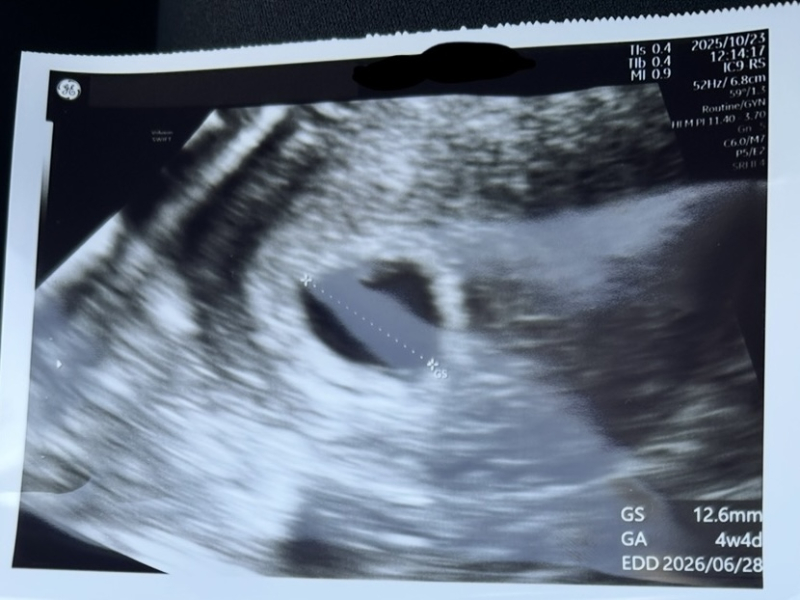

最後の生理が9/13で、10/15に妊娠検査薬で陽性反応が出ました。10/23に産科に行ったところ、生理周期が35日前後なことと胎嚢のサイズから妊娠5週目程度だろうとお医者さんから聞きました。2週間後には心拍確認できると思うよとの話があったため、11/8にまた産科に行ったのですが、胎嚢は大きくなってるけど、胎芽が10mmくらいほしいところ3mmくらいしかない。心拍も確認できない。稽留流産の可能性も考えられるから、11/14にもう一度心拍確認してみましょう。という話になりました。